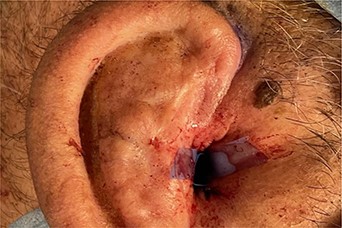

A 56- year old male was presented in the Outpatient Department of Otolaryngology Clinic with main complaint of complete aural atresia of the right ear. The clinical examination revealed that there was no external auditory canal in the right ear (Fig. 1) and hearing loss was altered (Fig. 2). There was no symptomatology in the left ear and the anatomic structures were completely normal. Blood test was normal, and there were no other medical issues from the personal history. The computed tomography (CT) scan and mainly the magnetic resonance imaging (MRI) of the temporal bone revealed no mastoid air cells and no external auditory canal and auricle (Figs 3 and 4). There was a normal anatomy of the internal auditory canal on both sides. Left side of the external auditory canal was normal. Diagnosis of this anatomical malformation was compatible with congenital atresia of the external auditory canal on the right temporal region. The patient decided to proceed to surgery many years after the first diagnosis. Some weeks ago, canalplasty and tympanoplasty were performed by our surgery team. During surgery, a graft has been obtained in order to formate the covering of the new canal. The incision was made behind the ear at the level of temporal bone, and the graft needed is removed from the temporal fascia and inserted as covering of the new canal. The aim is to create a new anatomic pathway resembling a normal external acoustic canal by drilling the atretic bone and removing the present tissue (Figs 5 and 6).